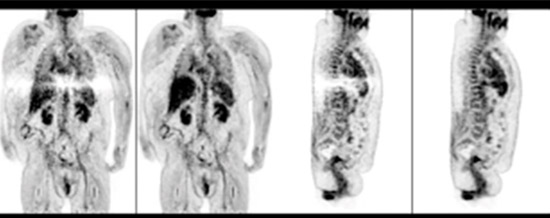

TOF reconstruction using SSS with tail-fitting (left image in each pair) and ×Clean (right image in each pair). The scatter correction artifacts seen with SSS plus tail-fitting are not present in the ×Clean reconstructions.

Scatter correction is essential to achieving high image quality. Yet conventional tail-fitting used to scale the single scatter simulation (SSS) result can show photopenic artifacts, particularly with larger patients or in the event of patient motion.

×Clean is a hybrid scatter correction method for reconstructing PET images. With its help, the Ingenuity TF PET/CT delivers improved image quality by reducing artifacts. ×Clean is a more robust method of scatter correction than using SSS with tail-fitting. It takes the result of SSS modeling and scales it by a factor derived from Monte Carlo simulation, a more computationally extensive form of modeling.

Instead of relying on patient boundary information, ×Clean uses SSS to approximate the shape of scatter contribution, and scales the SSS result by a factor determined by a low-count Monte Carlo simulation. This robust scaling method goes beyond tail-fitting and helps nuclear medicine professionals increase their diagnostic confidence regardless of patient habitus. With growing numbers of obese patients and an increase in longitudinal studies, achieving exceptional image quality and consistency are key aims today.